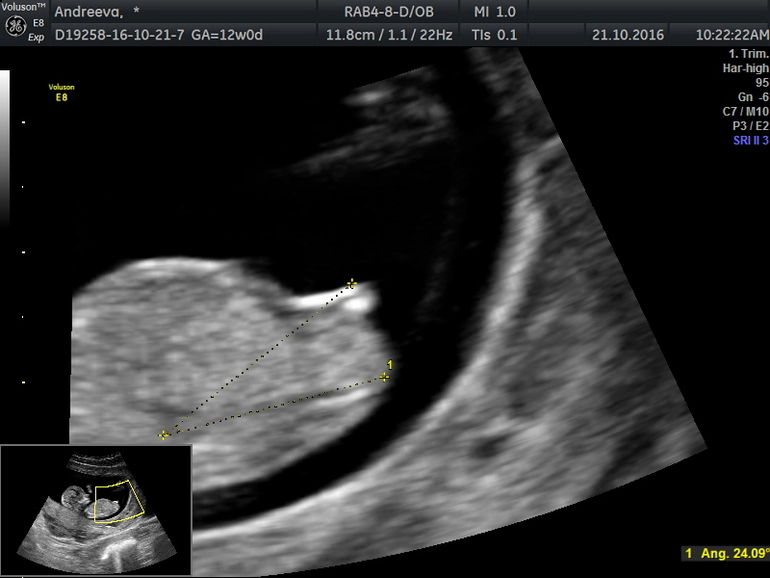

Вот нашла фото бугорка) мне по это фотке на 11+5длктор обещала парня)а сейчас говорит девочка